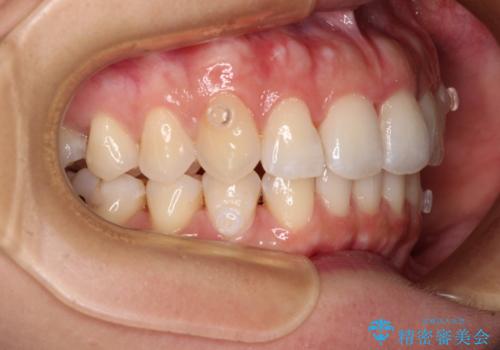

- 捻れた前歯が飛び出しており、口が閉じにくいとのことで来院された患者様です。

出っ歯というわけではないものの、前歯の捻転により口唇が押し出されている状態でした。

親知らずを抜去し、歯列全体を後方に移動させつつ、IPR(歯と歯の間を削る)でスペースを獲得し、インビザラインを用いて叢生を解消しながら前歯の突出を改善することとしました。

骨格的に上下正中がずれていたため、奥歯がしっかりと噛み合うか心配でしたが、ずれているなりに、しっかりとした咬み合わせとなりました。